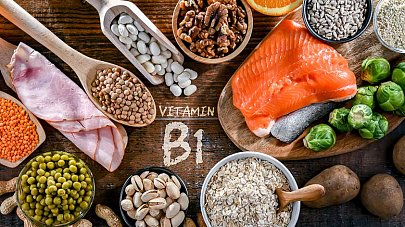

Витамин B1 — тиамин

Вещество, которое поддерживает работу сердца, мышц, нервной системы